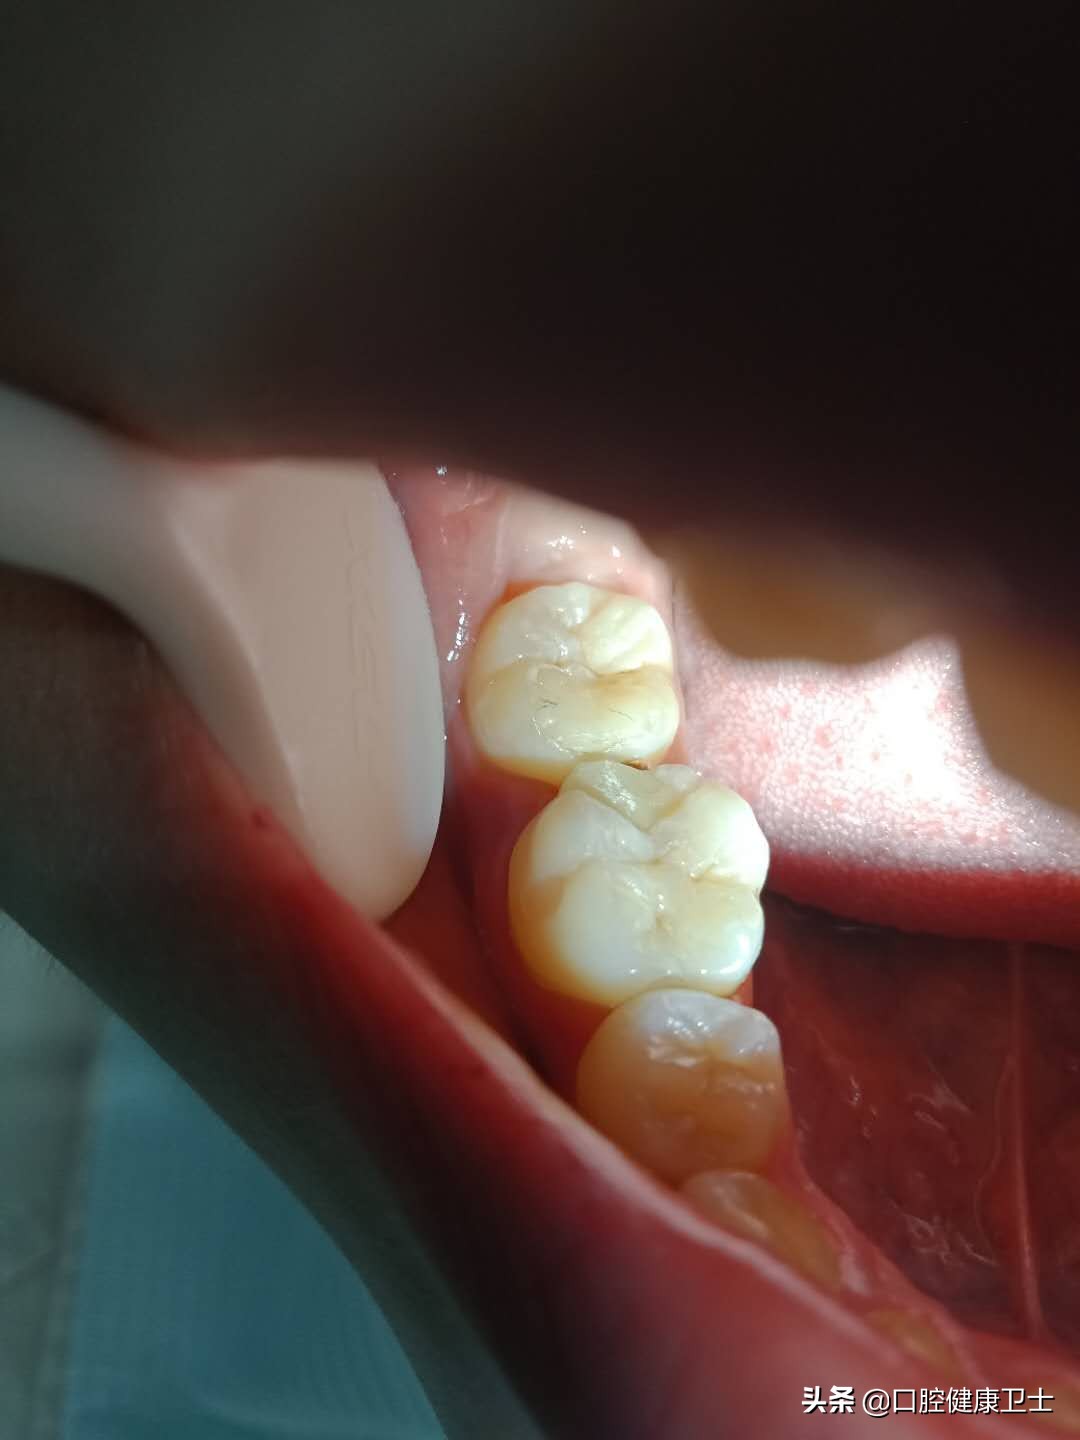

医生:你看,这是你一周前补得牙,现在检查发现了一些问题。

医生:充填体(就是补牙的材料),现在跟正常的牙体组织,不密合,正常的牙齿形态(就是正常的牙齿外形)没有恢复。

医生:还有问题呢,不仅仅是这些。你看,这张图片更明显,牙齿邻面形态很重要,可你这根本没有把正常邻面形态恢复出来,而是错误的把“牙缝”笼统地堵住了,这就是你出现疼痛的原因。